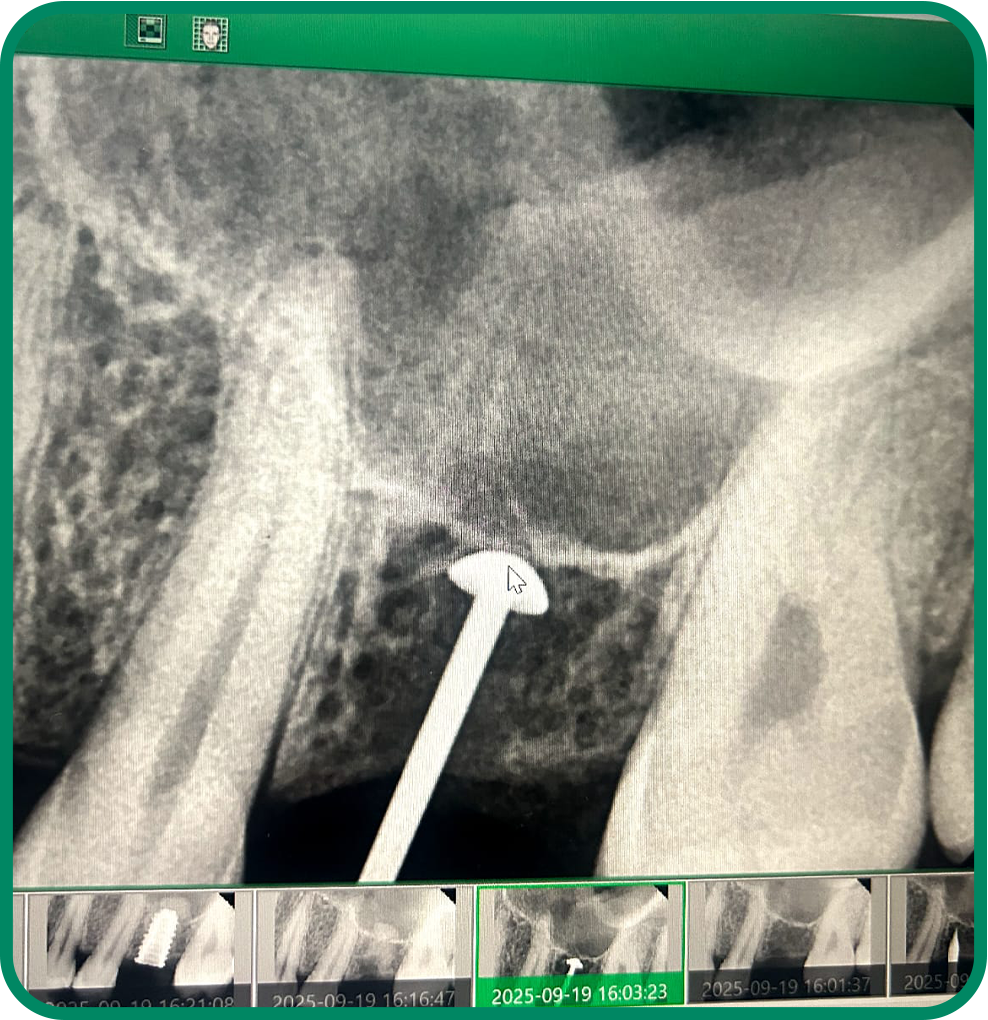

Painless RCT

Advanced root canal treatment designed to remove infection, relieve pain, and preserve your natural tooth comfortably and safely.